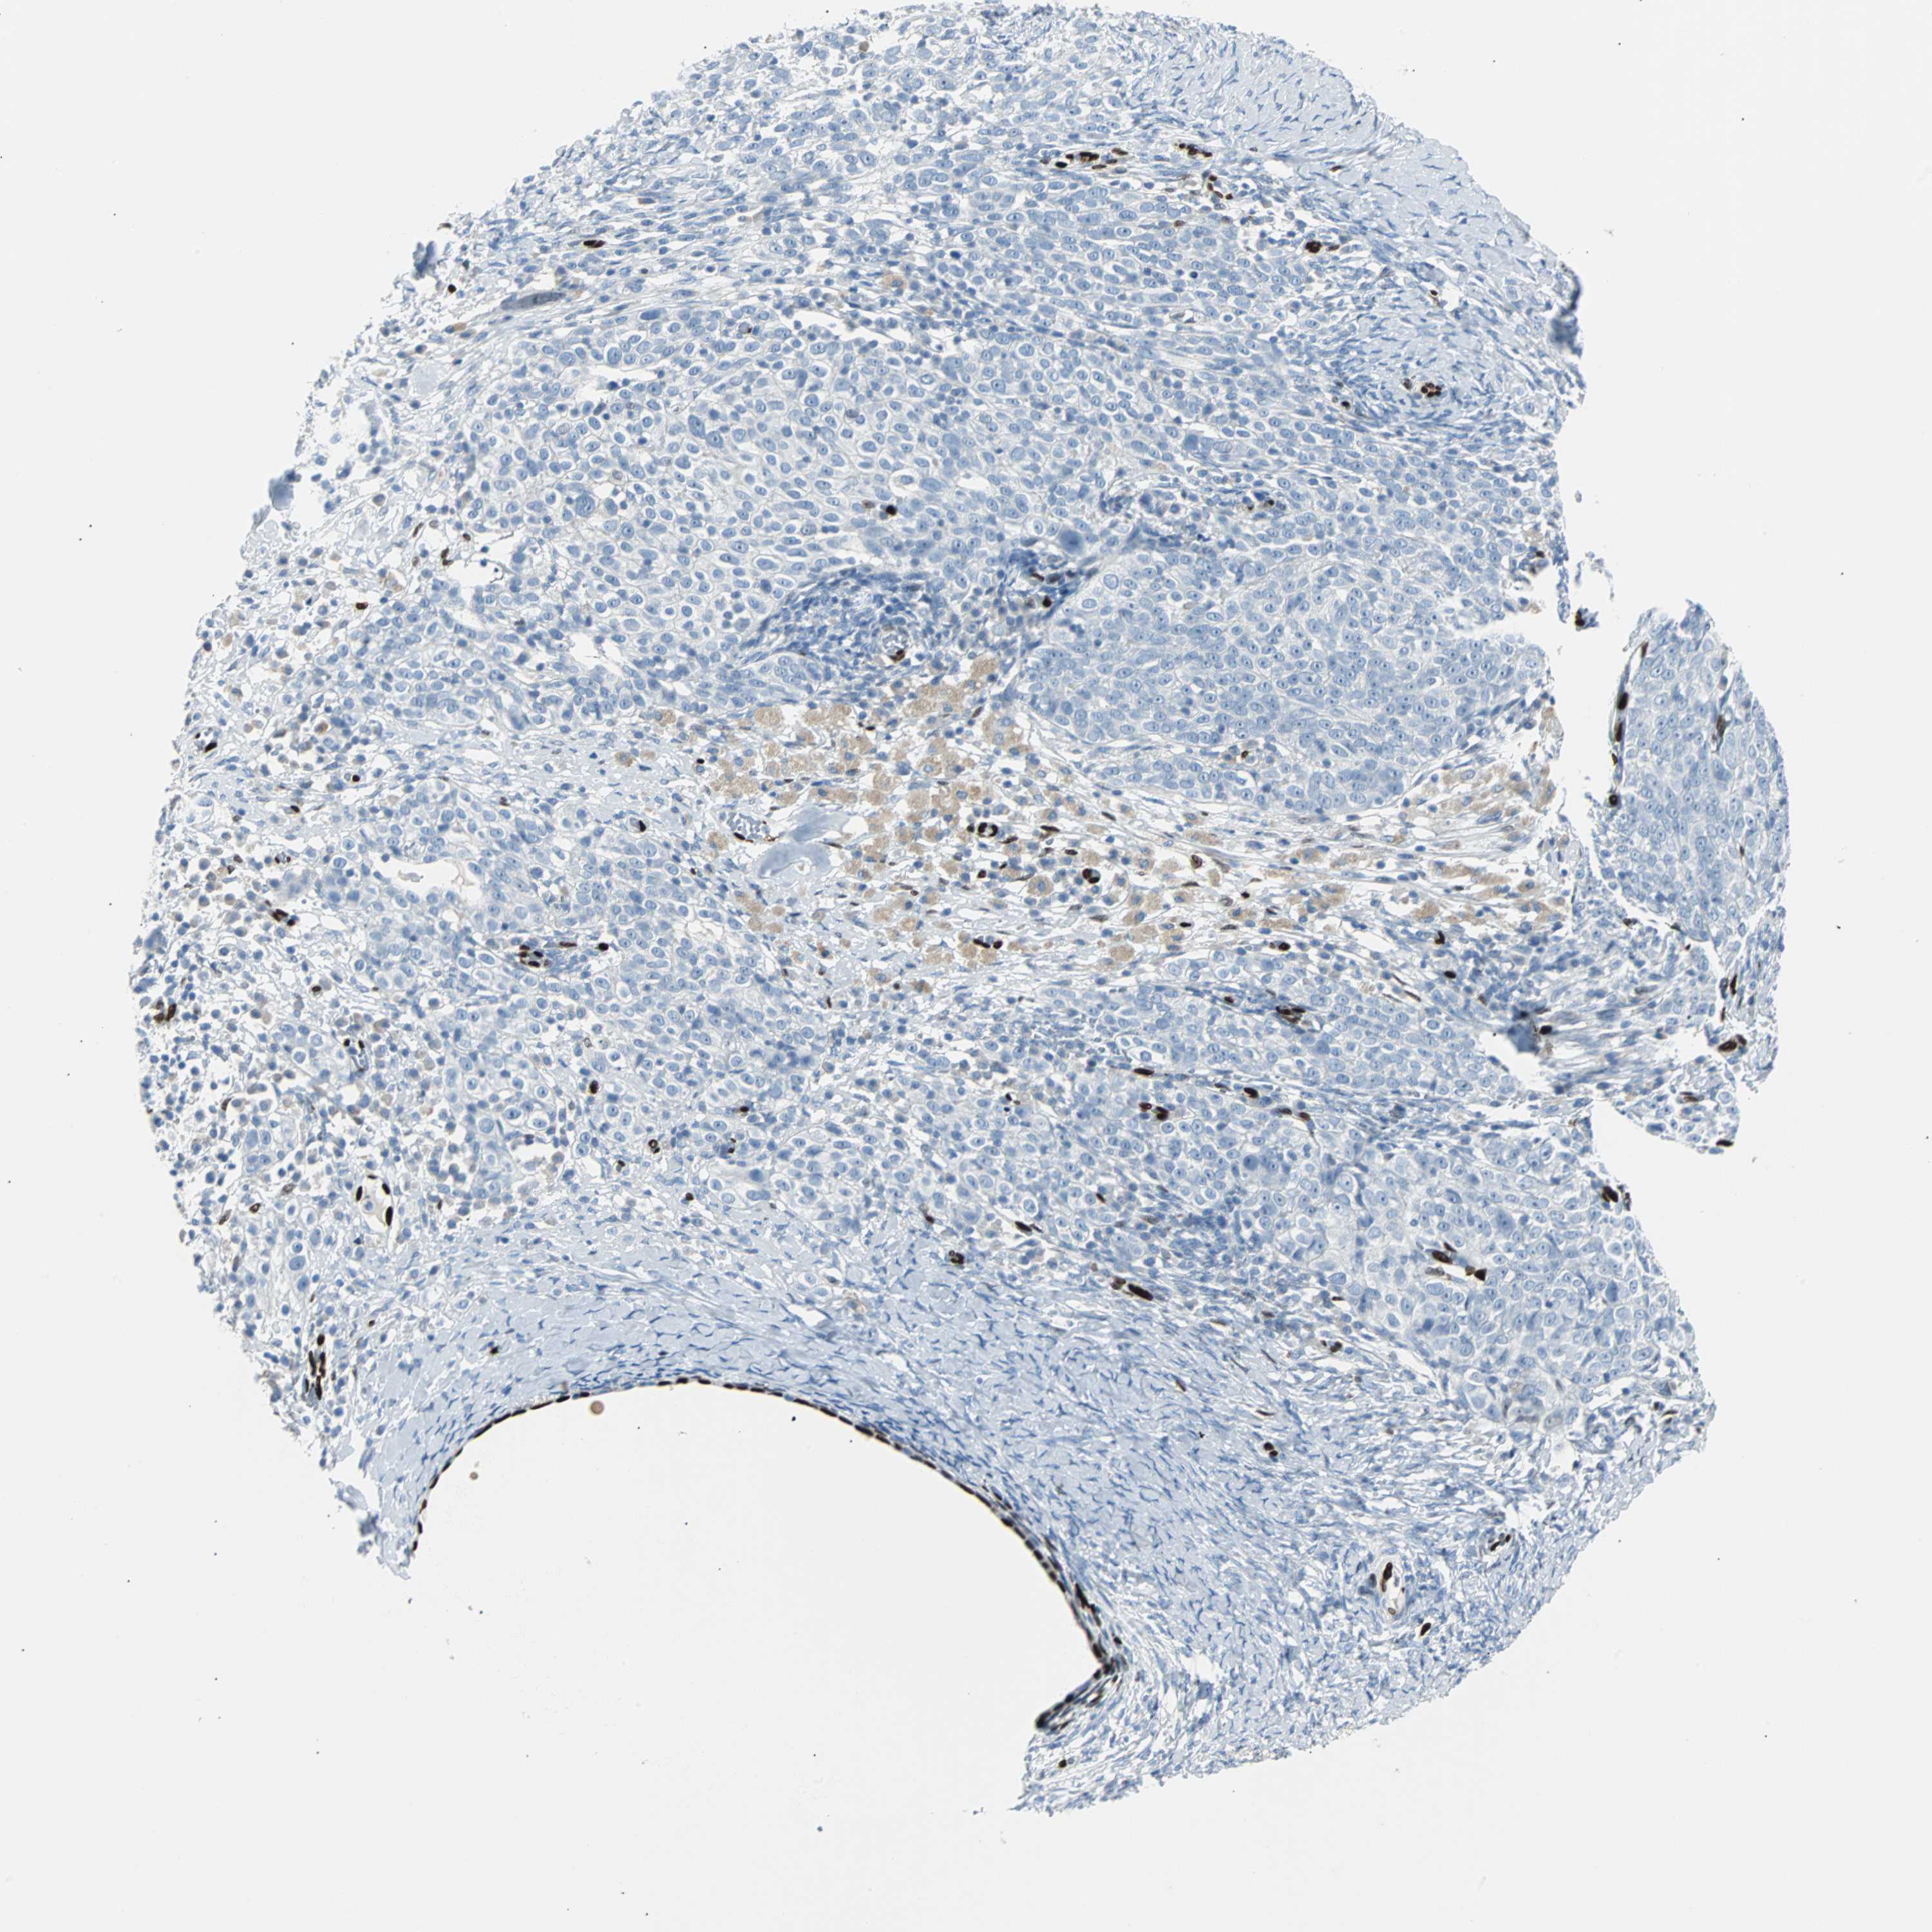

OVARIAN CANCER - Protein expressioni

A mouse-over function shows sample information and annotation data. Click on an image to view it in a full screen mode. Samples can be filtered based on level of antibody staining by selecting one or several of the following categories: high, medium, low and not detected. The assay and annotation is described here.

Note that samples used for immunohistochemistry by the Human Protein Atlas do not correspond to samples in the TCGA dataset.

Antibody stainingi

Antibody staining in the annotated cell types in the current human tissue is reported as not detected, low, medium, or high, based on conventional immunohistochemistry profiling in selected tissues. This score is based on the combination of the staining intensity and fraction of stained cells.

Each image is clickable and will lead to virtual microscopy that enables deeper exploration of all samples and also displays staining intensity scores, fraction scores and subcellular localization as well as patient and tissue information for each sample.

Antibody HPA024426

Antibody CAB007057

Staining

High

Medium

Low

Not detected

Intensity

Strong

Moderate

Weak

Negative

Quantity

>75%

75%-25%

<25%

None

Location

Nuclear

Cytoplasmic/membranous

Cytoplasmic/membranous,nuclear

Cystadenocarcinoma, serous, NOS